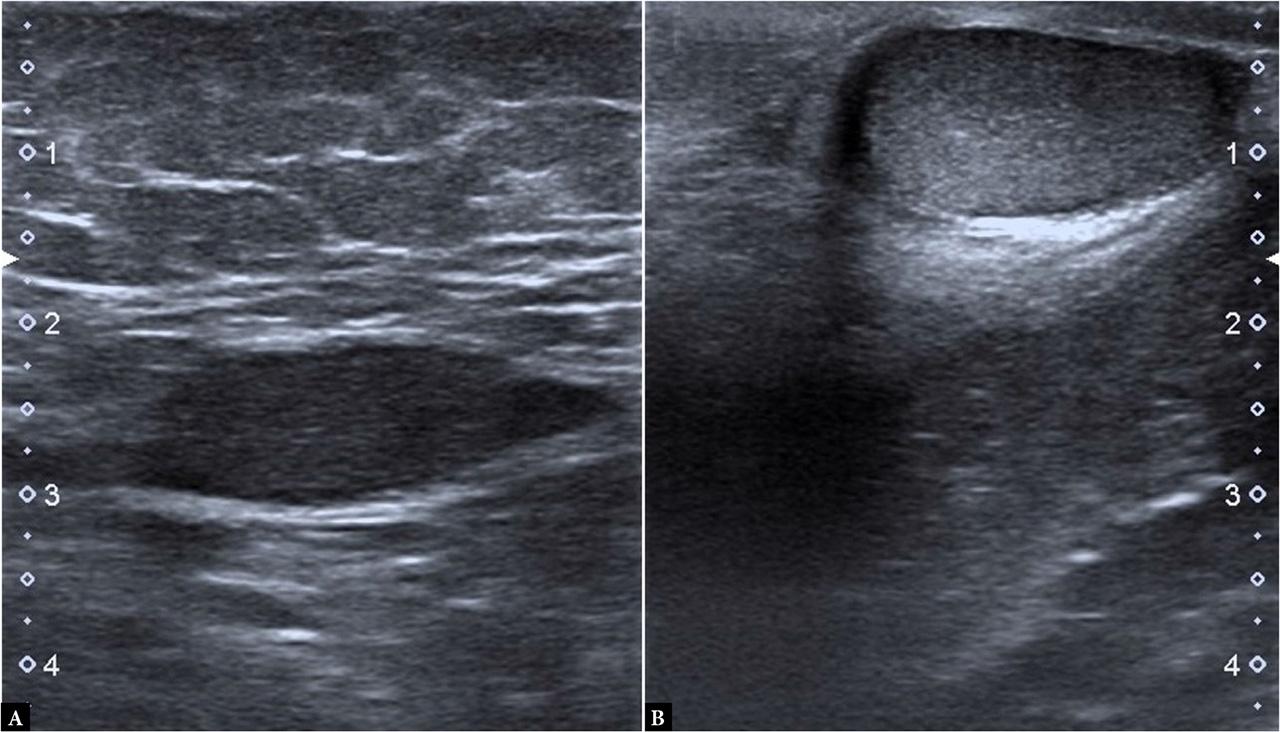

Gray-scale ultrasonography images in a 120-month-old boy. A. Deep plane undescended testis with reduced echogenicity and dimensions in the right inguinal canal. B. Image of left testis with normal echogenicity, located in the scrotum

Both the descended and undescended testes were analyzed by gray-scale US. Three planes (one mid-sagittal and two mid-axial planes) of both testes were measured in millimeters. The structure of the testes was assessed in gray scale with the same settings of the gain, focus, and depth. Echogenicity was scored in two grades: normal (homogeneous) and abnormal (inhomogeneous, hypoechoic or decreased echogenicity)(14).

Cryptorchidism (undescended testicle, UDT) refers to the inability of the intra-abdominal testicles to descend into the scrotum. UDT is the most frequent congenital genital abnormality found in boys, with a prevalence of 2–5% at birth and 1–2% by the age of three months. The testicles may be located in the inguinal canal in 72% of cases, in the prescrotal position in 20%, and in the abdominal cavity in 8% of cases(30). Histopathological findings associated with UDT include decreased germ-cell counts, lack of spermatogenesis, Leydig cell hypoplasia, and testicular fibrosis(30). Testicular volume of patients with UDT is lower than in the testes descended into the scrotum(30,31). Although the causes of growth and development impairments in UDTs have not been determined, one of the primary suggested causes is exposure to an abnormally high temperature environment(30). UDTs located deep or near the abdomen have been shown to have lower volumes due to higher temperature environments(30). Of the cases we examined, 34 unilateral UDTs had a lower volume and were less echogenic on US than the contralateral testes (Fig. 1 A). Dal Mo Yang et al. reported similar findings(30). USE is a simple non-invasive method for measuring tissue stiffness. Patients with cryptorchidism present with higher testicular stiffness than that found in normal testes due to increased intertubular fibrosis and testicular atrophy. As in our cases, patients with UDT show higher testicular stiffness compared to the normal testes due to increased intertubular fibrosis and testicular atrophy(30).